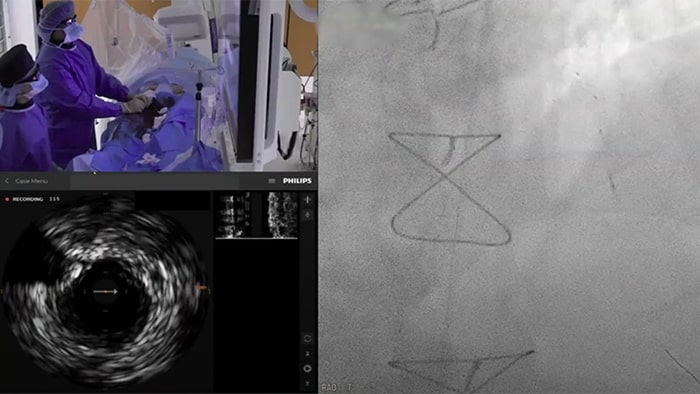

Asigne los valores de iFR directamente al angiograma, de modo que pueda ver con precisión qué partes de un vaso están produciendo la isquemia

El Dr. Justin Davies explica cómo el corregistro de iFR puede identificar la localización de la enfermedad y el impacto probable de la ICP antes de aplicar el stent.